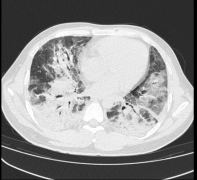

男子以为患普通感冒 经检查已是“大白肺”

男子以为患普通感冒 经检查已是大白肺 近期,东莞38岁的袁先生因发热、咳嗽、喘息,来到东莞市石碣医院治...